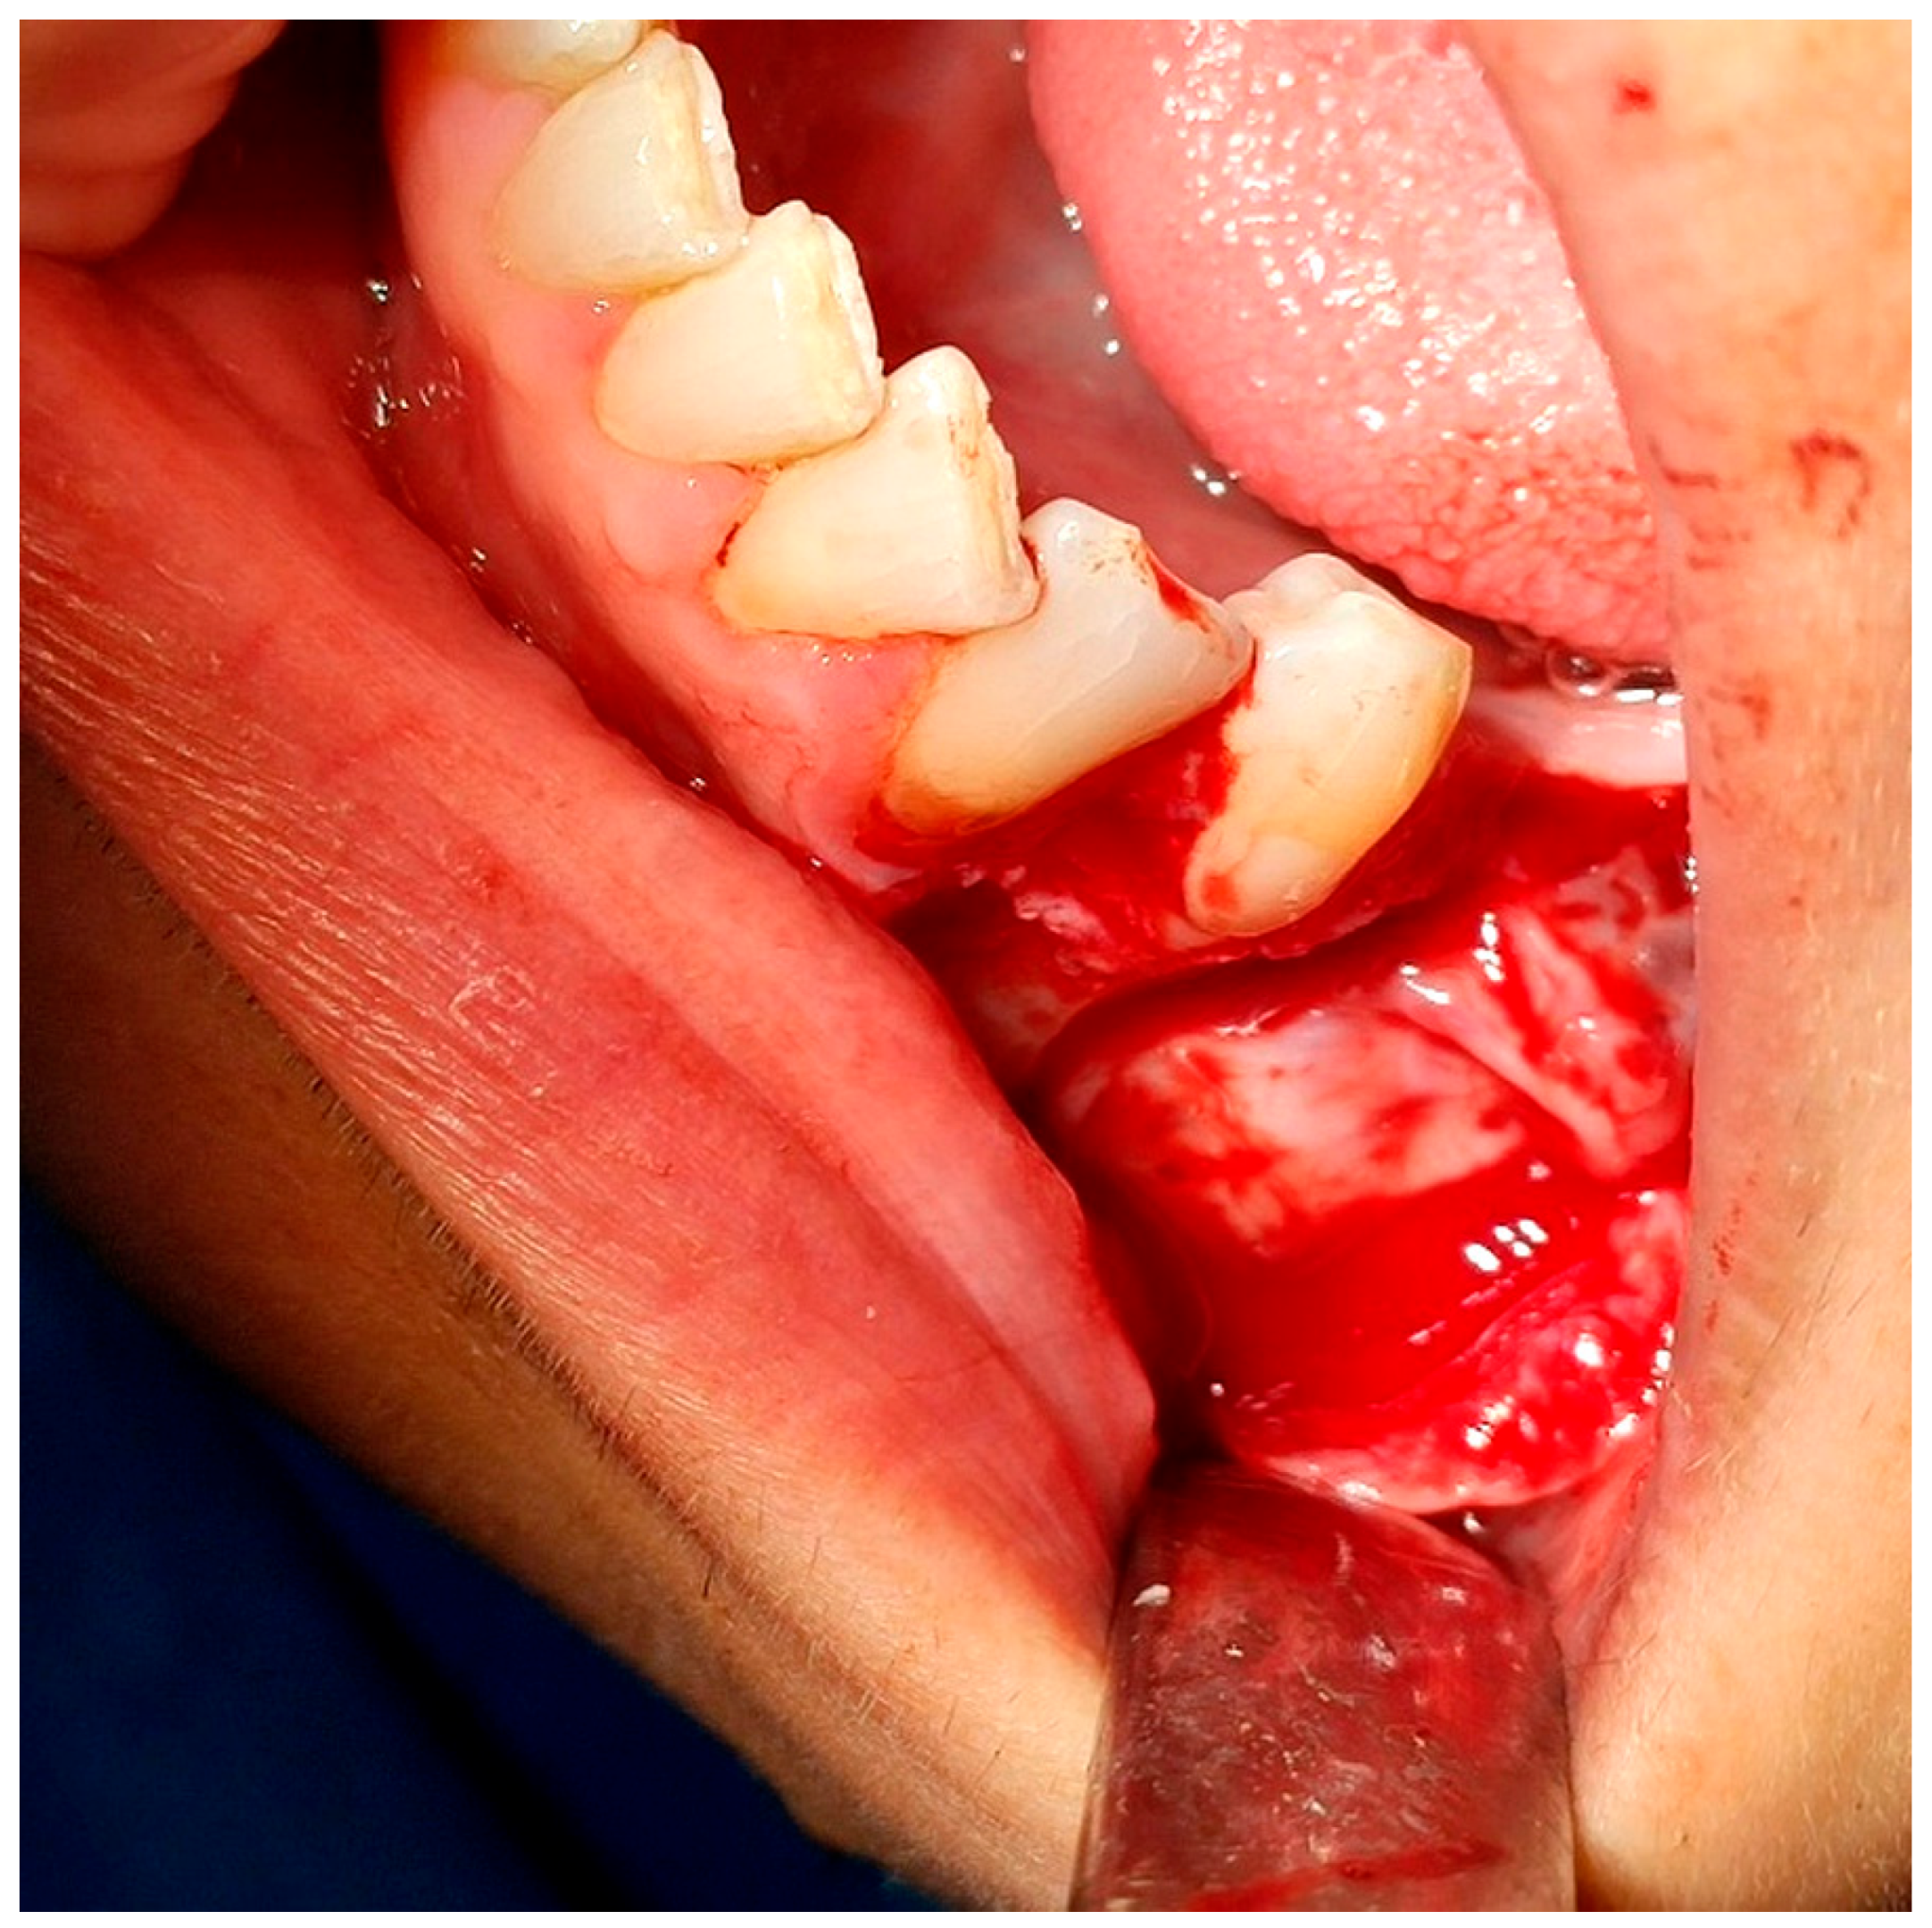

2.2. Surgical Intervention